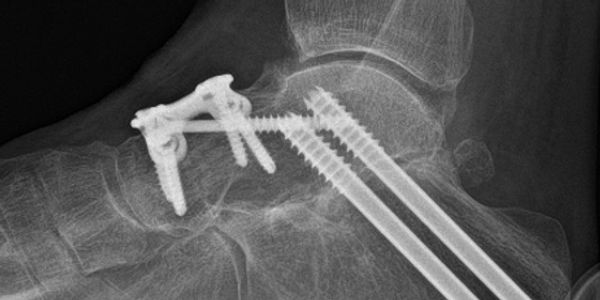

Hindfoot fusion surgery is used to treat severe arthritis, deformity or instability affecting the back of the foot, most commonly involving the subtalar, talonavicular and/or calcaneocuboid joints. These conditions can cause persistent pain, swelling and difficulty walking, particularly on uneven ground. Fusion stabilises the affected joints, removes painful movement and helps restore a more comfortable and stable foot.

The operation typically involves: